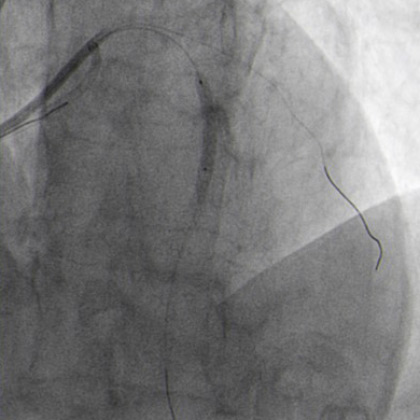

2.0 x 20 mm NC balloon predilatation (Figure 5.1)

Predilatation NC balloon (Figure 5.1)

Miracle exchanged with floppy wire to LAD. Guide wires position checked via controlateral injection (Figure 5.2).

Guide wires position via contralateral injection (Figure 5.2)